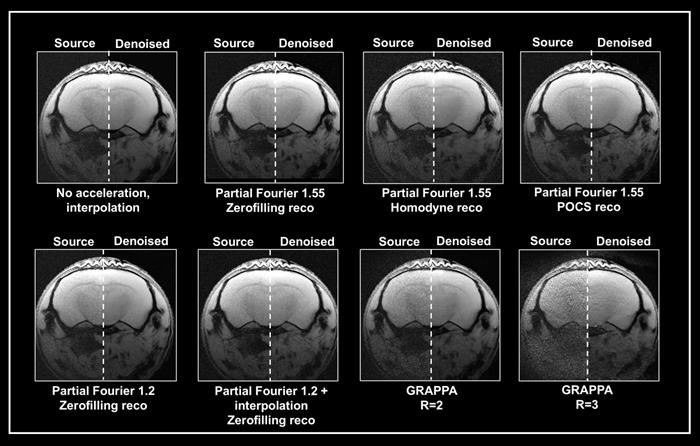

Ex vivo brain data were collected using either partial Fourier or the multi-coil generalized auto-calibrating partial parallel acquisition (GRAPPA) method (Fig 5). The data obtained without acceleration served as a reference. Acceleration resulted in up to a threefold reduction in acquisition times compared to the protocol without averaging.

Figure 5. Denoising of accelerated brain data. Ex vivo T1-weighted FLASH data of a fixed mouse head were acquired at 9.4 Tesla. Data were either acquired with no acceleration, with partial Fourier (in Read), partial Fourier and interpolation (1.35 in Read and Phase), or with multi-coil parallel imaging technique GRAPPA. For GRAPPA, an acceleration factor (R) of 2 and 3 was chosen, respectively. Partial Fourier images were reconstructed either with zerofilling, homodyne, or POCS, as indicated. All images are shown with no denoising (Source) and after denoising (Denoised) with a Strong network, applying a pre-denoising level of 50 % and denoising level of 70 %. Image Credit: Bruker BioSpin Group

A denoising level of 70% resulted in greater residual noise in data acquired with a partial Fourier 1.55 than in data acquired without acceleration. The effect was largest in homodyne-reconstructed data and weaker in zero-filled data.

Denoising of these accelerated datasets resulted in image blurring, which was largest in homodyne reconstructed images and lowest in zerofilling reconstructions.

When images were acquired using partial Fourier 1.2, they had less residual noise and appeared normal when denoised with 70%. Denoising, on the other hand, was ineffective when combining a partial Fourier with interpolation (1.35 in Read and Phase) and the source and denoised images had comparable appearances.

Grappa acceleration produced noisier images compared to partial Fourier capture. Reconstructing the collected data using the denoising method successfully reduced noise from the GRAPPA image acquired with an acceleration factor of 2.

However, in the image captured with an acceleration factor of 3, the noise is not totally erased. Moreover, reconstruction artifacts and loss of tissue contrast unrelated to the denoising reconstruction are visible.

This suggests that the method may be unable to deal with data with noise characteristics that differ from those used to train the networks. However, the outcome is determined by the parameters used for acquisition and reconstruction.